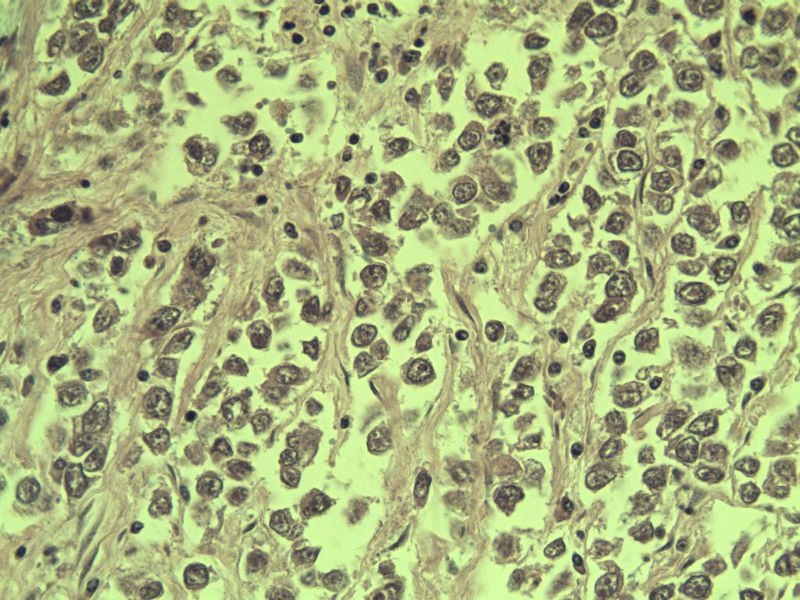

男 27岁 腹腔隐睾 5*3*2 cm, 切面灰红灰黄、实性、质中,请各位老师看看,是精原细胞瘤吗?感觉不像.腹腔隐睾图1

精原细胞瘤

典型的精原细胞瘤,隐睾易恶变